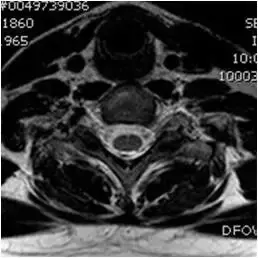

图39、轴向T2梯度回波图像。 左侧后外侧椎间盘突出伴压迫囊的前方。

图40、轴向T2梯度回波图像。椎间盘突出伴压迫硬膜囊前部。 注意到脊髓变形。 有椎管狭窄。 没有发现颈髓病。